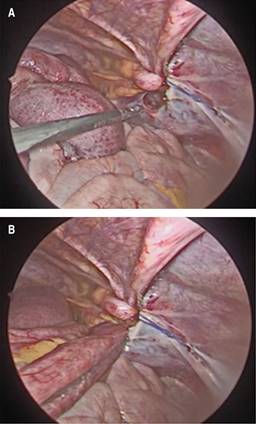

Se ingresó paciente para observación, hidratación por vía intravenosa con solución Ringer lactato y manejo médico sintomático persistiendo con sintomatología, por lo cual se indicó colocación de una sonda nasogástrica (SNG) y una tomografía computarizada (TC) de abdomen con contraste intravenoso. La TC de abdomen demostró obstrucción de intestino delgado con sospecha de hernia interna (Figura 1). Basado en hallazgos clínicos y radiológicos, se decidió realizar una laparoscopia diagnóstica de emergencia. Se identificó como origen de la obstrucción un asa de intestino delgado herniada en el espacio preperitoneal a través de un defecto peritoneal (Figura 2). No se identificaron datos de sufrimiento de asa, por lo cual se redujo la hernia y posterior cierre del defecto del peritoneo con poliglactina 910 2-0 puntos cruzados.

Figura 2: A) Se observa defecto peritoneal posterior a la reducción de asa de intestino delgado herniada. B) Asa de intestino delgado herniada en el espacio preperitoneal a través de defecto peritoneal.